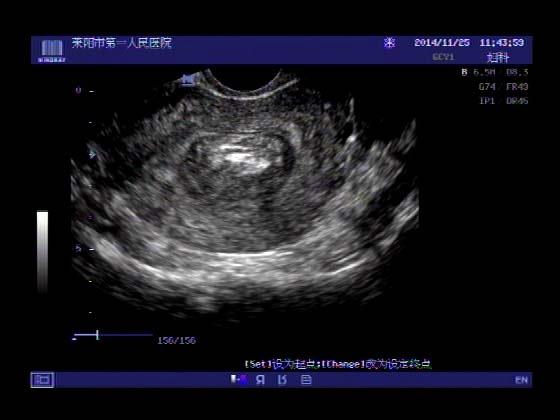

超声入门贴379---------粘膜下肌瘤(阴超的魅力)

女,43岁,月经量多3个多月,加重一个月

外院彩超检查提示:子宫后肌壁略高回声团------肌瘤?息肉?,盆腔少量积液

今天来我院检查:

巧妇难为无米之炊,经腹部超声确实很难定,阴超一目了然,乡镇医院诊断水平的提高更迫切的需要高档仪器的引进!